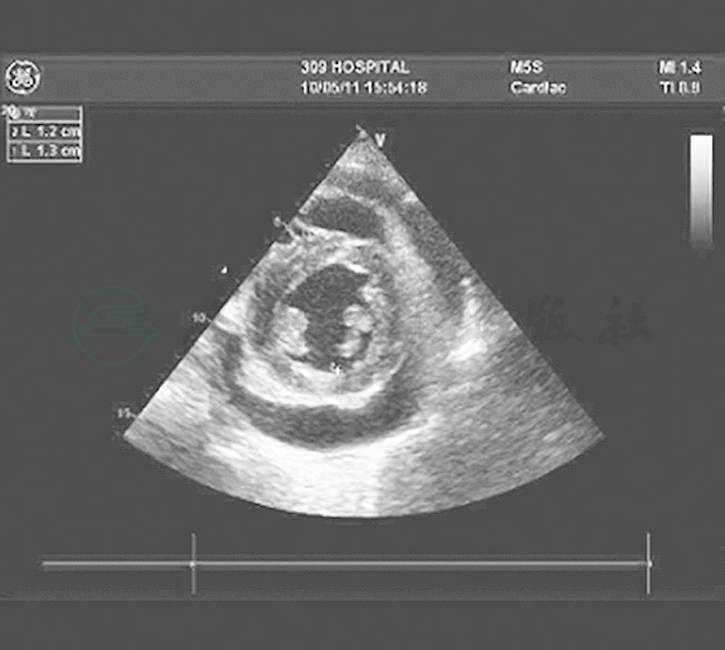

辅助检查:胸腔积液常规:黄色微浊,比重1.02,李凡他试验(+),白细胞1800×106/L,单核98%;胸腔积液生化:TP 24.5g/L、Glu 6.71mmol/L、Cl-100mmol/L;胸腔积液ADA 8.0U/L、LDH 42IU/L;胸腔积液结核抗体:ICTTB卡、快速TB卡均为阳性;痰涂片查抗酸杆菌阴性。腹腔积液结核抗体:ICT-TB卡、快速TB卡阳性。胸腹腔积液肿瘤标志物阴性。胸腔积液肿瘤标志物(卵巢)CA125 242.8U/ml;腹腔积液结核荧光定量PCR检测结果为阴性。ANA、抗-dsDNA等自身抗体谱阴性。胸部CT:右肺上叶、下叶及左肺上叶内可见多发斑片状、结节状高密度影,双侧叶间胸膜增厚,双侧胸腔积液,心包内见水样密度影,心包略增厚。胸部X线:左侧肺野见条索、斑点样高密度影,右上肺大片状高密度影。腹部、心脏超声:肝胆间隙、肝肾间隙、脾肾间隙、肝前间隙及肠管间隙均可探及不规则液性暗区,下腹部较深处约4.9cm。心脏超声可见心包中等量积液(图1~图4)。

图3 心脏横轴(左)及纵轴(右)均显示中等量心包积液